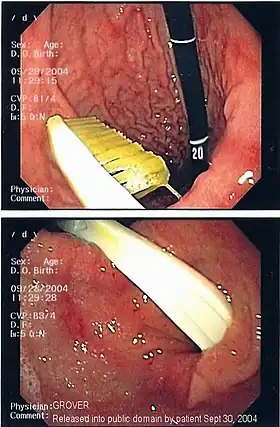

| An endoscopy image of the stomach, showing a foreign body in the form of a toothbrush. | |

One of the most common locations for a foreign body is the alimentary tract.

It is possible for foreign bodies to enter the tract from the mouth or rectum.